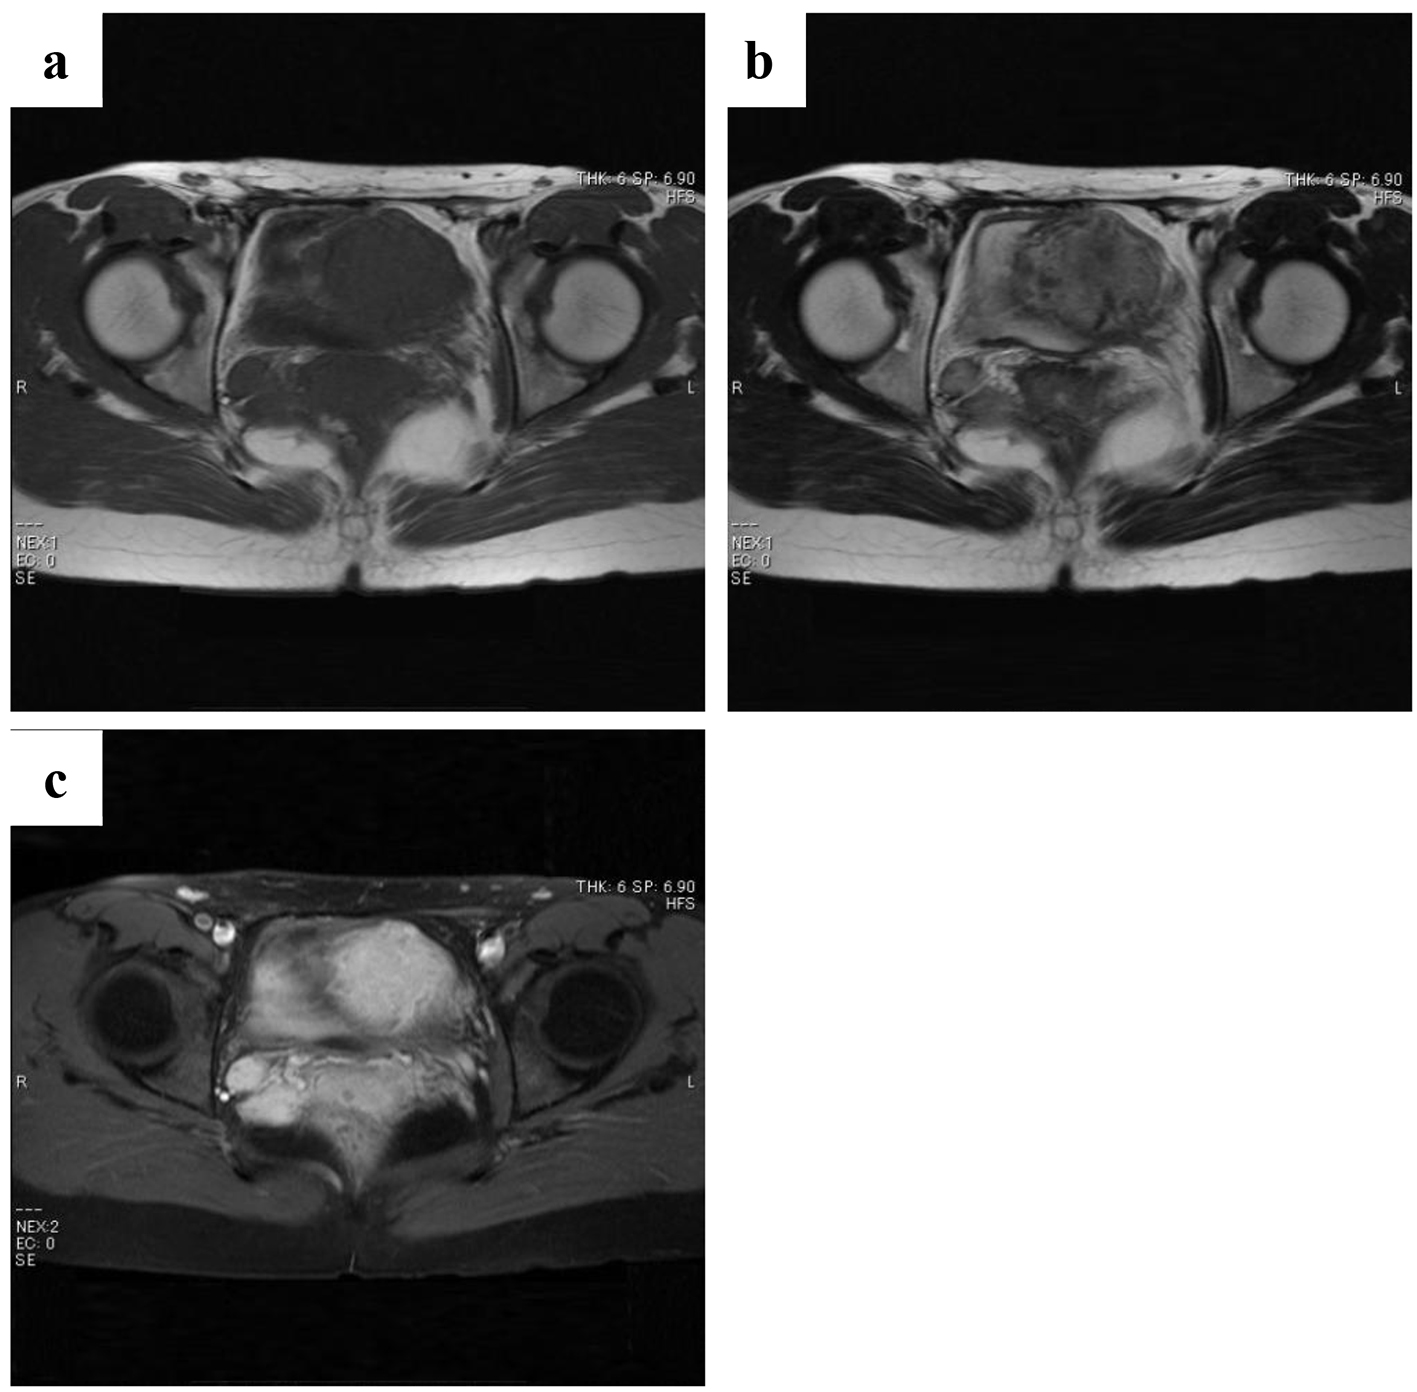

Figure 4. Magnetic resonance images of the two masses obtained at 3 years and 2 months after surgery (a: T1-weighted images; b: T2-weighted images; c: gadolinium contrast). These masses reached a maximum size of 1.8 cm in diameter.